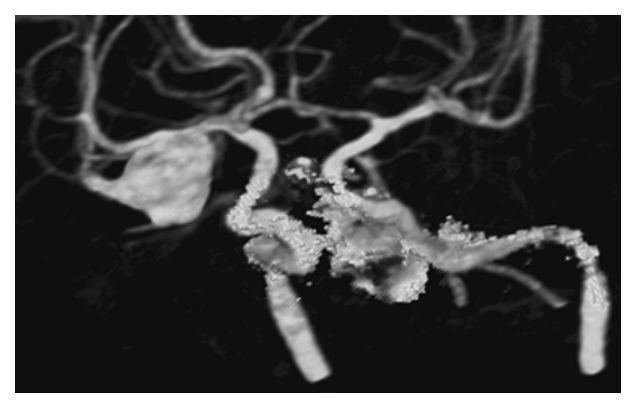

Neurovascular Compression Syndrome. MRA-TOF shows contact between the left posterior cerebral artery (PCA) (short arrow) and the left trigeminal nerve CN 5 (long arrow). In this individual, the vascular loop induced trigeminal neuralgia.